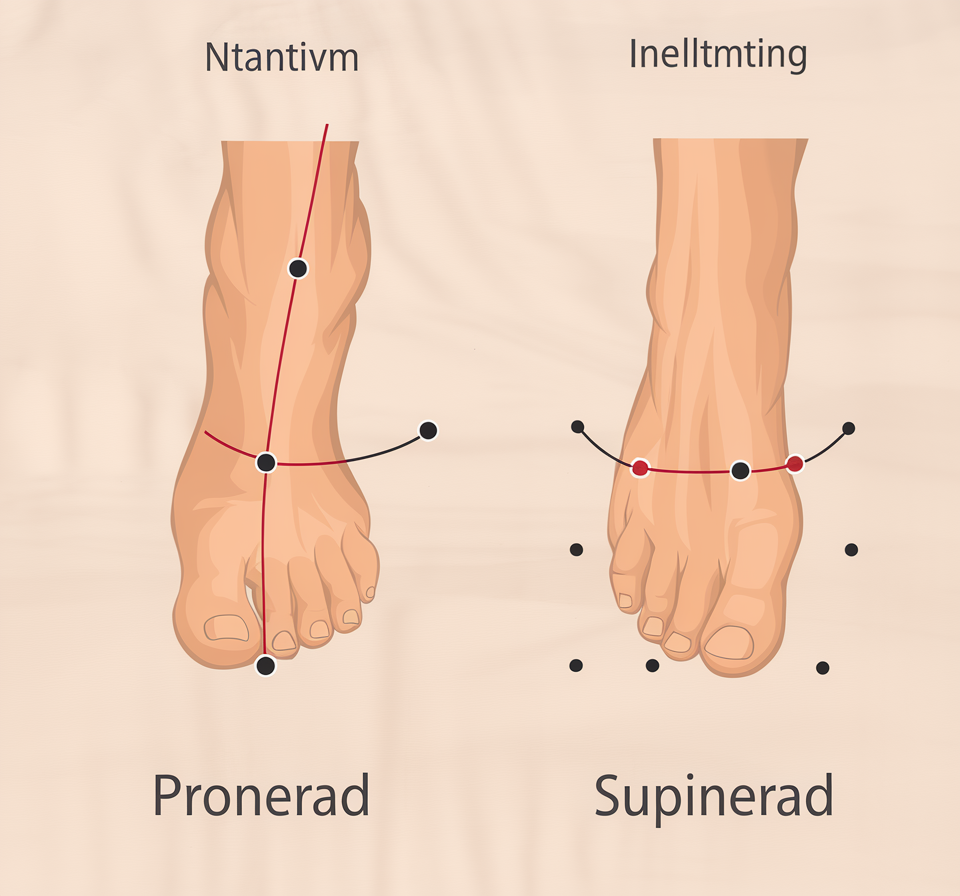

Fötterna bär upp hela vår kroppsvikt – så det är inte konstigt att fotproblem är vanliga. Från hälsporre och artros till brännande känslor och nervpåverkan – vi går igenom orsaker, symtom och möjliga behandlingar. Ta reda på vad dina fotsymtom kan bero på.